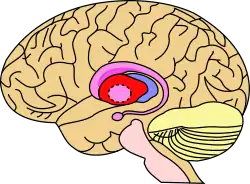

Putamen

The putamen (/pjutˈeɪmən/; from Latin, meaning "nutshell") is a round structure located at the base of the forebrain (telencephalon). The putamen and caudate nucleus together form the dorsal striatum. It is also one of the structures that compose the basal nuclei. Through various pathways, the putamen is connected to the substantia nigra, the globus pallidus, the claustrum, and the thalamus, in addition to many regions of the cerebral cortex. A primary function of the putamen is to regulate movements at various stages (e.g. preparation and execution) and influence various types of learning. It employs GABA, acetylcholine, and enkephalin to perform its functions. The putamen also plays a role in degenerative neurological disorders, such as Parkinson's disease.

![]() Putamen (in red) shown within the brain | |